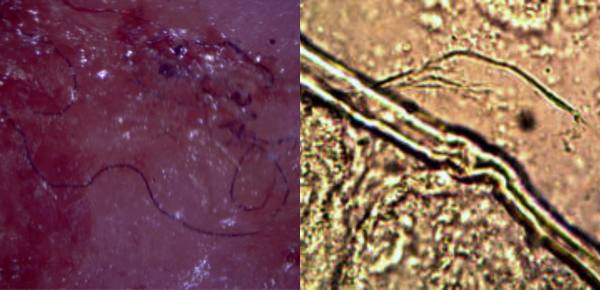

U człowieka opisano zespół objawów nowej choroby, zwanej morgellons. Po raz pierwszy została opisana w 2001 roku u gospodyni domowej, pracującej jako technik laboratoryjny, pani Mary Leitao. U jej dwuletniego synka zaobserwowano zmiany, które pod mikroskopem ujawniły czerwone, niebieskie i biało-czarne włókna. Nazwa Morgellons została zaczerpnięta z listu sir Thomasa Browna z 1690 roku, opisującego chorobę charakteryzującą się „epidemią ciężkich włosów” na plecach dzieci w Langwedocji.

Oczywiście tzw. rządowe instytucje zaprzeczały początkowo istnieniu tej choroby. Jednakże pojawiająca się coraz większa liczba pacjentów zmusiła niejako CDC do przeprowadzenia badań. Raport, jaki ukazał się w 2006 roku, zaprzeczał nowej chorobie. Kolejny raport, także zaprzeczający, miał się ukazać w 2009 roku w czasopismach medycznych. Do dnia dzisiejszego jednakże nie ukazał się. Pojawiło się natomiast DUŻO PUBLIKACJI Z RÓŻNYCH STRON ŚWIATA, GDZIE WŁAŚNIE WOJSKO BAWIŁO SIĘ W PANA BOGA.

Objawy. Chorzy opisują swój stan jako kłujący, podobny jak po ukąszeniu przez owady ból w miejscu zaczerwienienia. Opisują to także, jakby coś chciało od wewnątrz przebić skórę. Te subiektywne odczucia są obiektywnie obrazowane przez rany przypominające ukłucia owadów, okrągłe zaczerwienienia z owrzodzeniami w środku. Badania mikroskopowe uwidaczniają wystające z wewnątrz nitki. Badanie morfologii przeprowadzone u takich chorych wykazuje niedokrwistość. Inne wyniki badań wykazują zaburzenia w pracy gruczołów dokrewnych, takich jak tarczyca, czy trzustka. Niski poziom CD-57 i podwyższony poziom markerów stanu zapalnego, tj. białka CRP.

Sama Fundacja Badań Morgellons ma w swoich kartotekach już 15 000 chorych. Takich chorych opisywano zarówno w USA, jak i Kanadzie, Anglii, Australii, RPA, Holandii i Rosji. Choroba występuje mniej więcej po okresie 10 lat sypania trwałych smug. Włókna są doskonale widoczne pod dużym powiększeniem, rzędu 200-300 razy, niestety nie dysponujemy w Polsce takimi „powiększalnikami”. Można je także oglądać w świetle ultrafioletowym.

Co do pacjentów w Trójmieście, widzieliśmy kilka przypadków, jednakże nie udowodniono istnienia włókien z powodu braku odpowiedniego sprzętu. Objawy zdecydowanie różniły się natomiast od zwykłych ukąszeń owadów, czy alergii i nie chciały goić się przez długi okres, pomimo stosowania typowego leczenia. Opisy z publikowanych prac podają, że zmiany zawierają twarde przezroczyste włókna, które są bardzo odporne na ekstrakcję. Wszyscy chorzy podają uczucie podobne do tego, jakby coś się chciało przebić ze środka na zewnątrz.

Najwięcej informacji można uzyskać z badań Instytutu Carnicom (link TUTAJ).

Badania przeprowadzone przez Kaiser Permanent Nothern California w latach 2006-2008 zidentyfikowały 115 pacjentów z tą chorobą, co daje częstotliwość 3,65 na 100 000 ludzi. U chorych w 59% wykrywa się deficyt poznawczy, nie dający się wyjaśnić IQ. 63% chorych miało istotne kliniczne dolegliwości somatyczne. Wszystkie rany były trudno gojące się. Badania kalifornijskie są istotne, ponieważ teren zamieszkuje 3-milionowa populacja.

Poniżej kilka zdjęć typowych dla Morgellons. Pierwszy zestaw zdjęć przedstawia zmiany skóry pleców i zdjęcie mikroskopowe wychodzących z nich włókien.